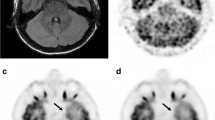

18F-FDG PET image of a 3-year-old female patient weighting 12.8 kg with a diagnosis of focal cortical dysplasia (FCD) by biopsy was reconstructed into brain axial views of 600, 300, 150 and 60 s (a–d). As the acquisition time was reduced to 60 s, the lesion was still identifiable. (e) Histopathology finding of the patient, characterized by architectural dysplasia and dysmorphic neurons

A 5-year-old man diagnosed with FCD IIId with Rasmussen encephalitis by pathology. The images showed lesions in left cerebral hemisphere for the group 60–600 s (a–d). Diffuse hypometabolism and focal hypermetabolism were observed in the left cerebral hemisphere, and the lesion detectability was visible from 600 s to 60 s. (e) Pathological image showed neuron degeneration and necrosis with astrocytic hyperplasia